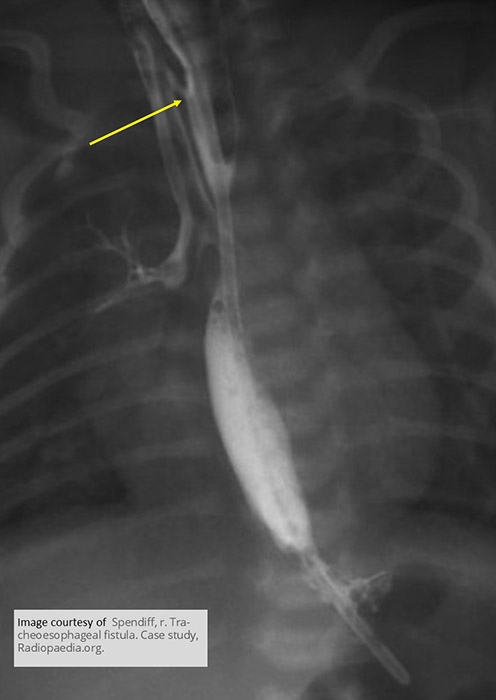

What is the best imaging modality to identify the fistula in acquired TEF?

Fluoroscopy with water-soluble contrast.

What contrast should be used if fluoroscopy is required for TEF?

Water-soluble contrast only (high aspiration risk).